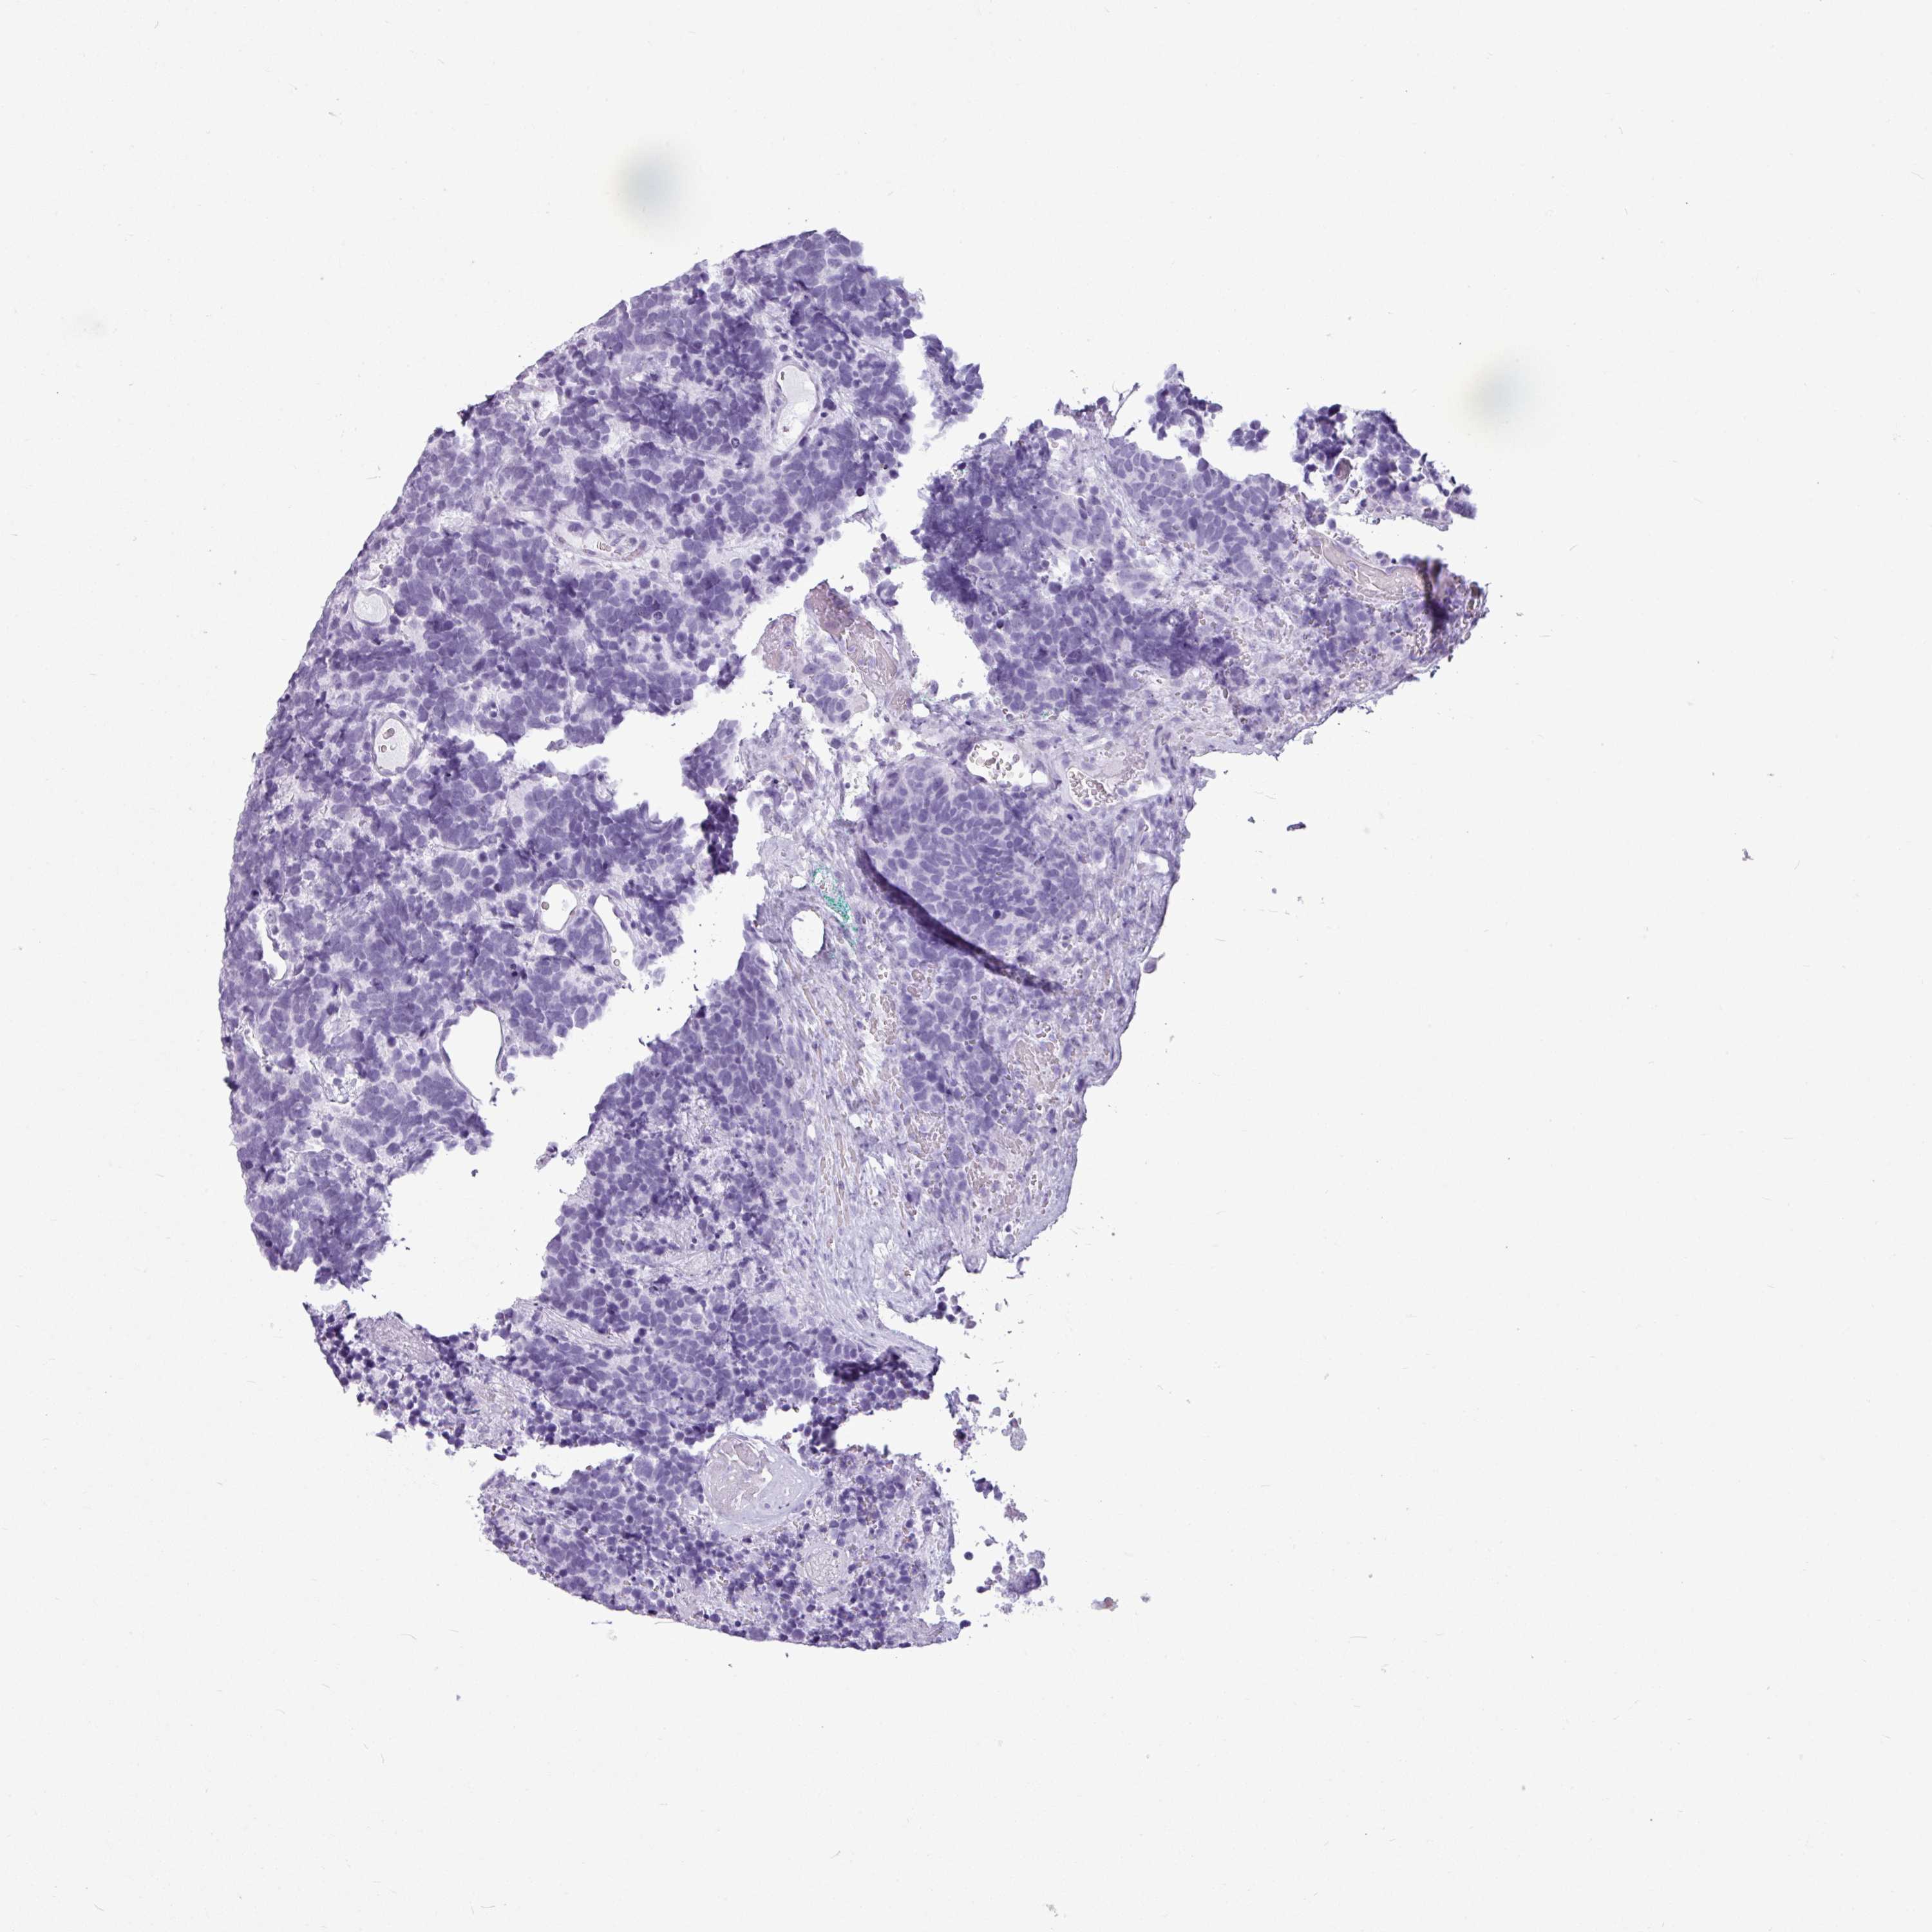

AMY1C